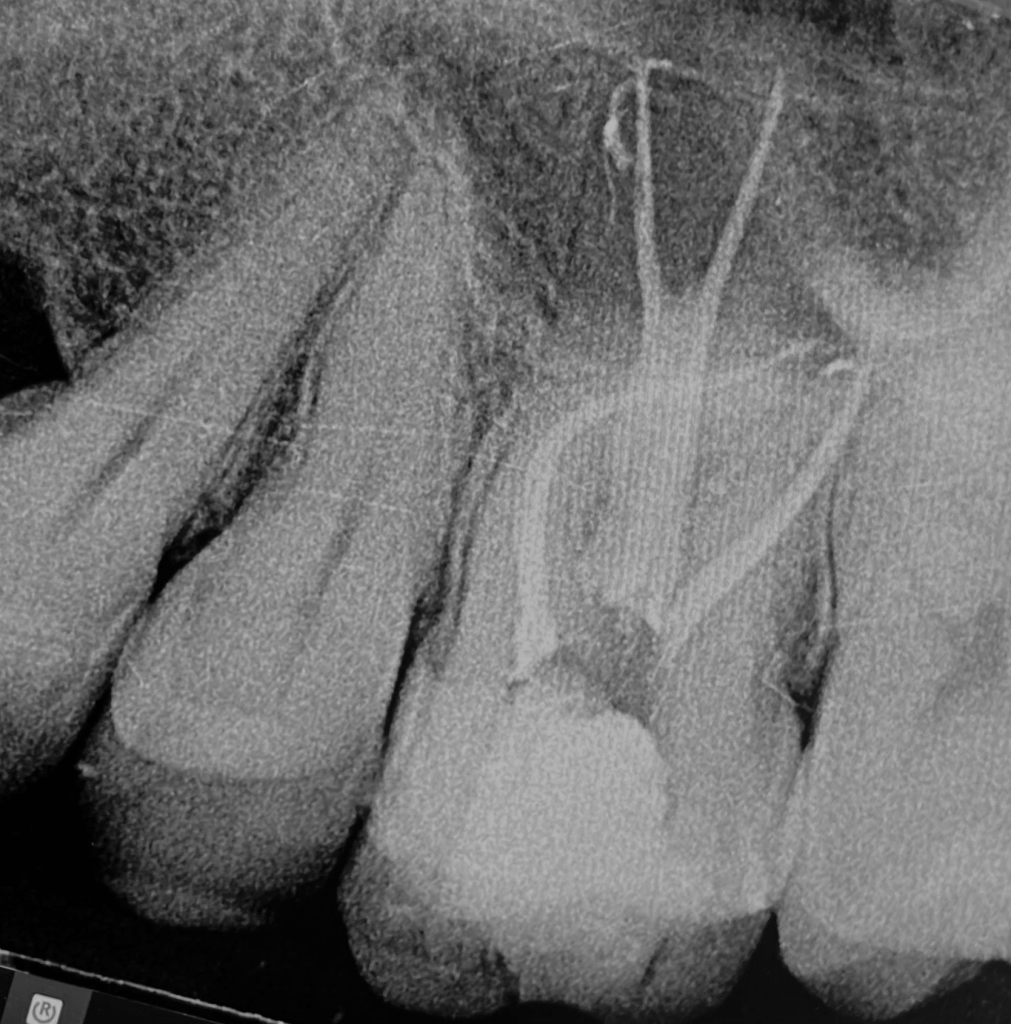

2 Limas rotas + reco Preendo